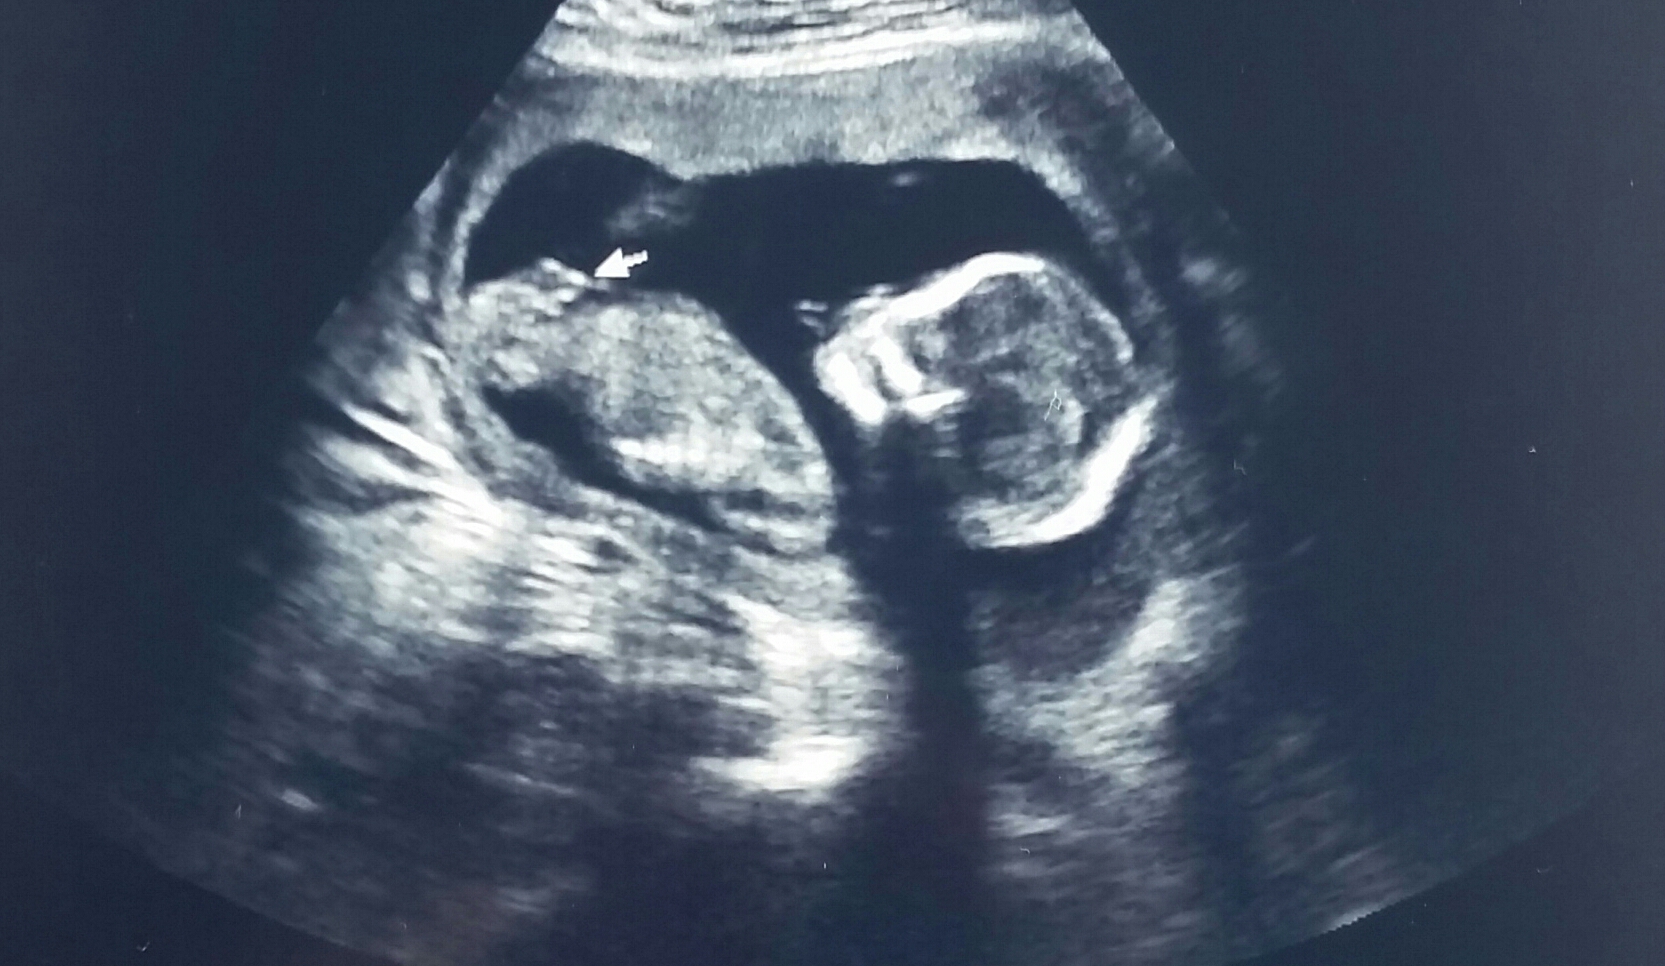

I went at 15 weeks and 3 days for a gender ultrasound which I know I saw horror stories of 15 week ultrasounds being wrong. I was told it was a boy from this photo and that was the best she could show us of the "turtle". My next ultrasound will be with my doctors office in 3 weeks which I will be 19 weeks so we should be able to confirm then. Does anyone believe it could be a mistake and possibly a girl or definitely looks like a boy. Has an early "turtle theory" been wrong for anyone? Just curious now what this precious baby is but definitely ready for my 19 week ultrasound.

• I went at 15 weeks and 3 days for a gender ultrasound which I know I saw horror stories of 15 week ultrasounds being wrong. I was told it was a boy from this photo and that was the best she could show us of the "turtle". My next ultrasound will be with my doctors office in 3 weeks which I will be 19 weeks so we should be able to confirm then. Does anyone believe it could be a mistake and possibly a girl or definitely looks like a boy. Has an early "turtle theory" been wrong for anyone? Just curious now what this precious baby is but definitely ready for my 19 week ultrasound. Thank you all in advance!

Anyways, based on my internet research only (I'm not a tech...I'm not qualified whatsoever), I would believe that your tech who said boy was correct.

• I have 2 boys and am currently carrying a girl and none of my gender determination shots were from this angle. I would have my doubts based solely on this picture. But if the tech saw multiple angles she is probably right.